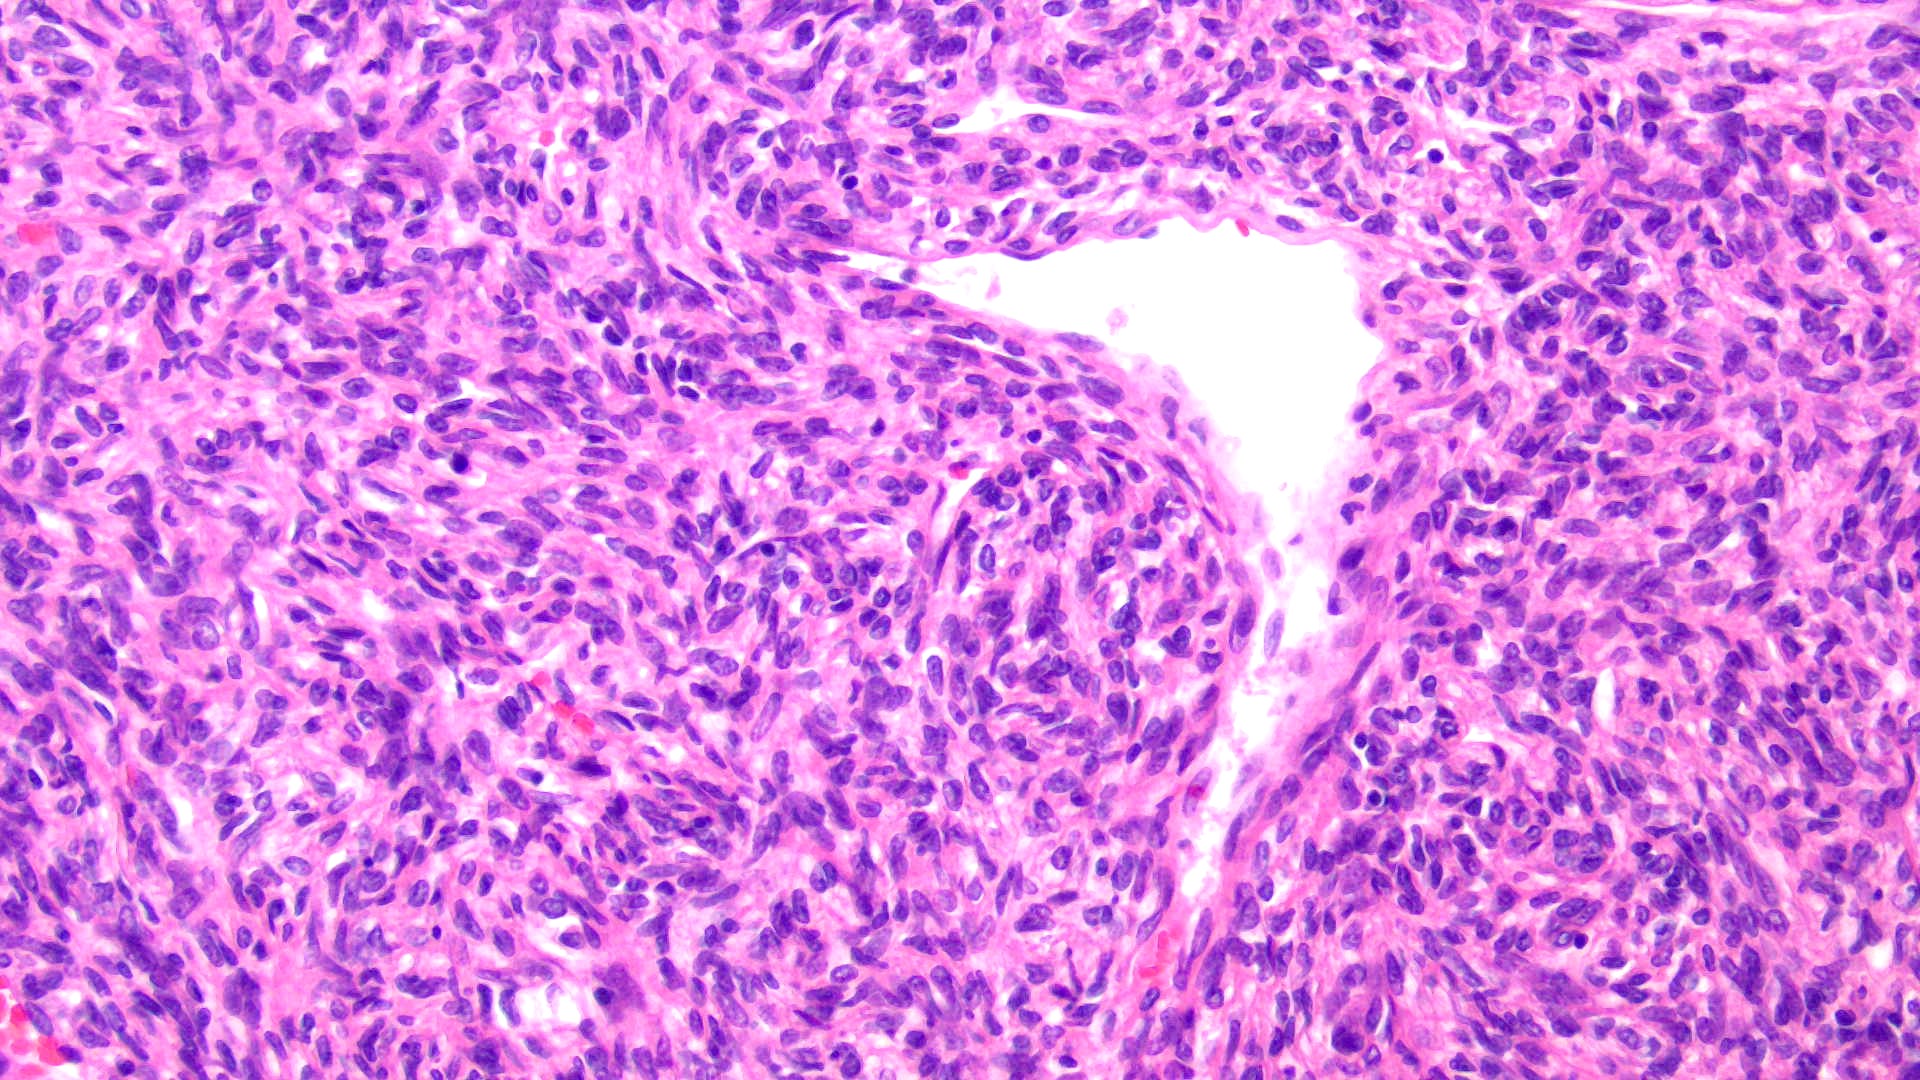

42-year-old male with hypoglycemia, altered mental status, and large skull-based mass with prominent veins. Diagnosis and genetics? (H&E and CD34)

Answer: B: Hemangiopericytoma / NAB2-STAT6 fusion